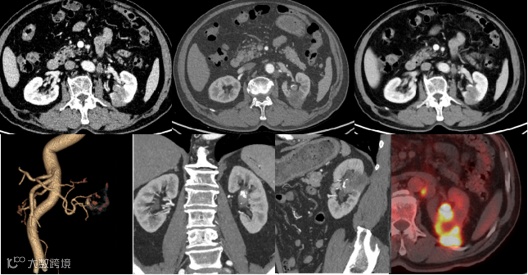

病例3

男,75岁

主诉:无痛性肉眼血尿半月

现病史:无明显诱因下肉眼血尿,无尿急尿痛,偶伴小血块,血尿间断发作,无排尿费力。无畏寒发热,无其余不适

影像号:

2022-12-28 PET-CT 影像号:PET221626

2023-02-06 肾动脉血管CTA成像 影像号:2717933

影像学表现